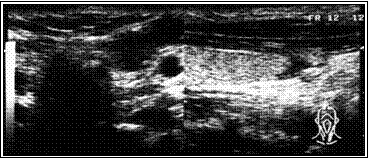

Ниже иллюстрируется клинических случай больной Л, 18 лет. При УЗИ в левой доле обнаружен кистозно-дегенерированный узел 21х9х15 мм. Кистозная дегенерация составила около 75% от объема. При диагностической тонкоигнольной пункционной биопсии дважды получены клетки фолликулярного эпитерия щитовидной железы (кубического и пролиферирующего) и элементы пунктата кистозной полости.

Расчетный объем узла ЩЖ составил 1,4 мл (= 2,1 * 0,9 * 1,5 * 0,52).

Под контролем УЗИ больной произведена пункция узла, аспирировано около 0,5 кистозного содержимого, после чего в полость образований введено 1.0 мл этилового спирта, что составило около 2/3 от расчетного объема узла.

На приведенных ниже эхограммах демонтрируется динамика регрессии в течение года.

А. Эхограмма до склеротерапии